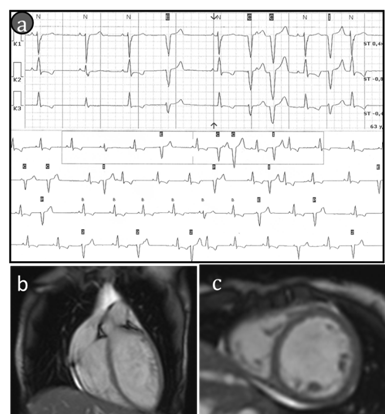

At examination of the patient a 6-minute walk test was 415m. The 12-lead electrocardiogram (ECG) showed sinus tachycardia (heart rate 104 BPM) with left axis deviation, left bundle branch block (QRS duration 124ms), normal corrected QT interval and nonspecific ST-T wave abnormalities. Holter monitoring of ECG showed an intermittent left bundle branch block (to 33%/24h); frequent premature ventricular contractions (PVCs) to19600/24h, coupled PVCs (158 couplets/24h), ventricular triplets (44/24h), non-sustained ventricular tachycardia (4 to 7 ventricular complexes with HR max up to 130BPM). ECG-strip demonstrating ventricular arrhythmia is presented in Figure 1A. The patient underwent echocardiography which demonstrated left ventricular dilatation with global systolic dysfunction, hypokinesis and moderate mitral valvular regurgitation. Diastolic and systolic diameters of the left ventricle were 57 and 47mm, respectively. The left ventricular (LV) ejection fraction (EF) was 33% and LV global longitudinal strain was -11,6%. Cardiac magnetic resonance imaging (MRI) confirmed criteria of DCM: LV dilatation (LV end-diastolic volume 177 ml, LV end-systolic volume 124ml) and global systolic dysfunction (LVEF 30%). Hypertrabecular structure of myocardial apex was found also.MRI findings of cardiomegaly are presented in Figure 1B, Figure 1C. Endomyocardial biopsies were examined, and no genetic markers of 8 cardiotropic viruses using PCR method were detected. Histological findings showed non-specific diffuse changes in myocytes (their size and nuclei varied) and interstitial fibrosis, no conclusive evidence of inflammation. Hormonal evaluation included follicle-stimulating hormone (140.2IU/L; menopausal range 25.8-134.8IU/L), luteinizing hormone (70.5IU/L; menopausal range 7.7-58.5IU/L), estradiol (201pmol/L; menopausal range 0.1-505pmol/L). Thyroid function test was consistent with subclinical hypothyroidism (thyroid stimulating hormone 6.98mIU/L; normal range 0.35-4.94mIU/L). Mini-Mental State Examination cognitive test was 20 scores (11-19 scores: medium dementia; 20-23 scores: mild dementia). Ultrasonography revealed a moderate thyroid hypoplasia. The patient refused to receive hormone replacement therapy. Pelvic ultrasonography revealed hypoplastic uterus, and the bilateral ovaries could not be clearly seen. However, the patient was capable to menstruate only with the support of estradiol and progesterone. X-rays examination of collarbones, extremity phalanges and cranium was performed to exclude mandibuloacral dysplasia taking into account signs of severe microretrognathia and adipose tissue thinning (lipodystrophy). Mandibuloacral dysplasia (MAD; OMIM 248370) is a rare, genetically and phenotypically heterogeneous, autosomal recessive disorder characterized by skeletal abnormalities including hypoplasia of the mandible and clavicles, acroosteolysis, cutaneous atrophy and lipodystrophy. X-rays revealed no evidence of MAD-specific bone dysplasia, i.e. distension of fontanel cranial sutures, dental abnormalities, clavicle hypoplasia and distal phalange acroosteolysis findings are presented in Figure 2.

Figure 1Findings of cardiac examination.

(A)ECG strip demonstrates the premature ventricular contractions (to 100PVCs/1h). (B &C) cardiac MRIetc-cardiac MRI features of cardiomegaly (b-long-axis and c-short-axis post contrast views ,there is no sub-epicardial or mild-myocardial pattern of late gadolinium enhancement).